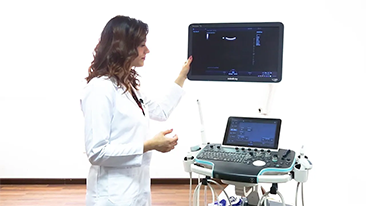

Der hochaufl?sende 21,5 Zoll gro?e LED-Monitor liefert gestochen scharfe Bilder und ideale Rahmenbedingungen. Der in der Neigung verstellbare Touchscreen l?sst sich ganz leicht bedienen und auf die jeweiligen Bedingungen der klinischen Umgebung anpassen.